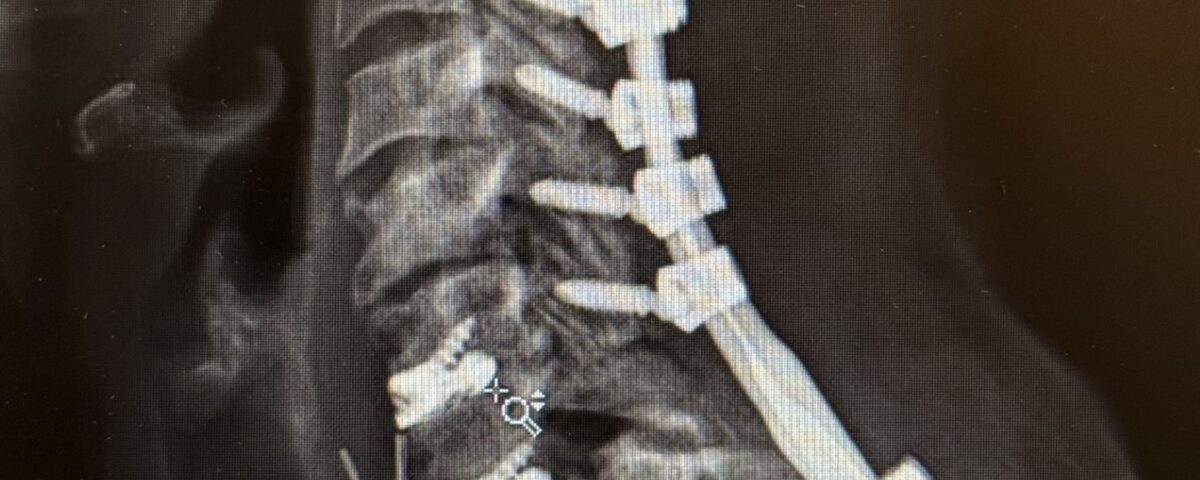

The patient underwent a one-day, two-stage procedure. Stage 1 was a C6-7, C7-T1 anterior cervical discectomy and fusion with reduction of the anterolisthesis and correction of the kyphosis.

Stage 1 was immediately followed by Stage 2 which was extension of her posterior instrumentation and fusion from C3 down to T3. Neuro-navigation was used to assist with the difficult anatomy of the upper thoracic spine.

The patient had an uneventful postoperative course with significant improvement in her preoperative symptoms and is now able to maintain a good posture (Fig 2 right).